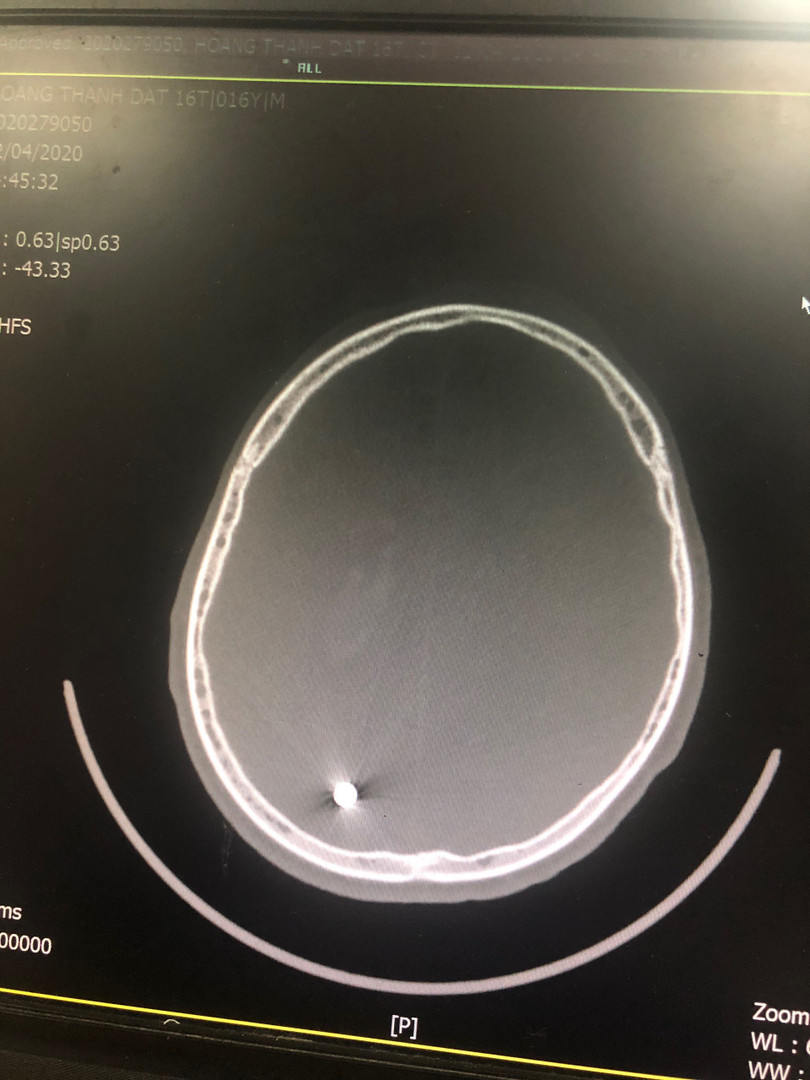

Tại Bệnh viện Hữu nghị Việt Đức, các bác sĩ đã tiến hành cấp cứu kịp thời cho người bệnh, Kết quả chụp X-quang phát hiện vết thương nhỏ đường kính 0,55mm xuyên qua não từ trán đến đỉnh chẩm bên phải. Vết thương xuyên dọc theo chiều dài não đã khiến em Đ. bị liệt nửa người bên trái.

| Phim chụp vết thương viên đạn xuyên qua não của bệnh nhân Đ. Ảnh: BVCC |

Các bác sĩ đã tiến hành phẫu thuật lấy viên đạn trong não cho bệnh nhân. Sau mổ, bệnh nhân Đ. tỉnh táo, vẫn bị liệt nửa người do thương tổn não.